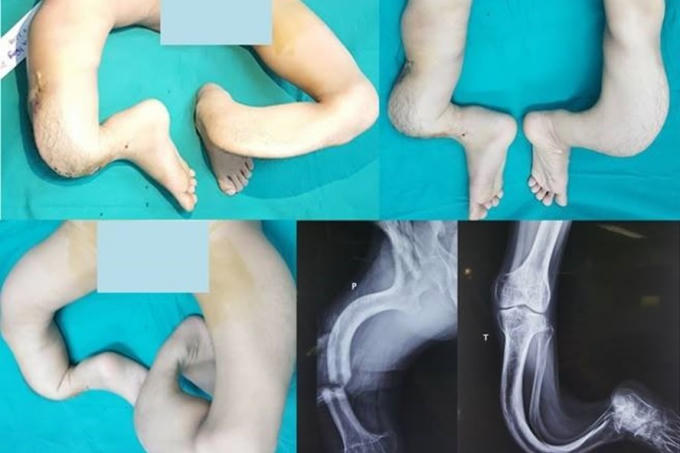

Sinh ra, Nguyễn Mạnh Hùng đã có một đôi chân khác biệt với tất cả mọi người. Càng lớn lên, đôi chân của cậu càng bị uốn cong nặng nề hơn. Đôi chân đó dần trở nên méo mó vẹo vọ và không giống ai. Nhiều người gọi đôi chân của cậu là đôi chân giống như "rễ cây".

GS.TS Nguyễn Thế Hoàng - Phó Giám đốc Bệnh viện Trung ương Quân đội 108 chia sẻ, khi nhìn thấy đôi chân của Hùng, các bác sĩ chuyên ngành đều rất kinh ngạc vì một dị dạng phức tạp đến kỳ lạ và khó tin mà suốt cả hơn 30 năm làm nghề, họ chưa bao giờ nhìn thấy.

"Hình ảnh X-quang cả hai chi dưới cho thấy toàn bộ hệ thống xương khớp ở vùng đùi, cẳng chân và bàn chân đều bị biến dạng cong vẹo và phức tạp theo nhiều chiều, nhiều hướng khác nhau. Chiều dài xương hai bên là hoàn toàn khác biệt. Các cấu trúc phần mềm quan trọng để che phủ, nuôi dưỡng và bảo đảm hoạt động chức năng cho cả hai chân như da, cân, cơ, gân, mạch máu và thần kinh cũng bị thay đổi hoàn toàn. Do không đi lại tỳ nén nên xương bị thưa loãng nặng.

Ngoài ra, dù có chỉnh thẳng được đi nữa thì theo đo đạc chênh lệch của hai chân sẽ là trên 20cm. Với chênh lệch này, bệnh nhân cũng sẽ không thể đi lại bình thường. Đây thực sự là một thách thức quá lớn và quá khó khăn đối với chúng tôi nếu muốn chỉnh hình cho bệnh nhân trở lại hình hài giống như người bình thường". GS.TS Nguyễn Thế Hoàng chia sẻ.